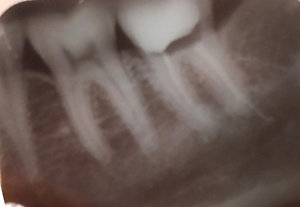

• К сожалению, нам не известна первоначальная картина. На данном снимке определяется выведение материала за верхушку дистального корня.